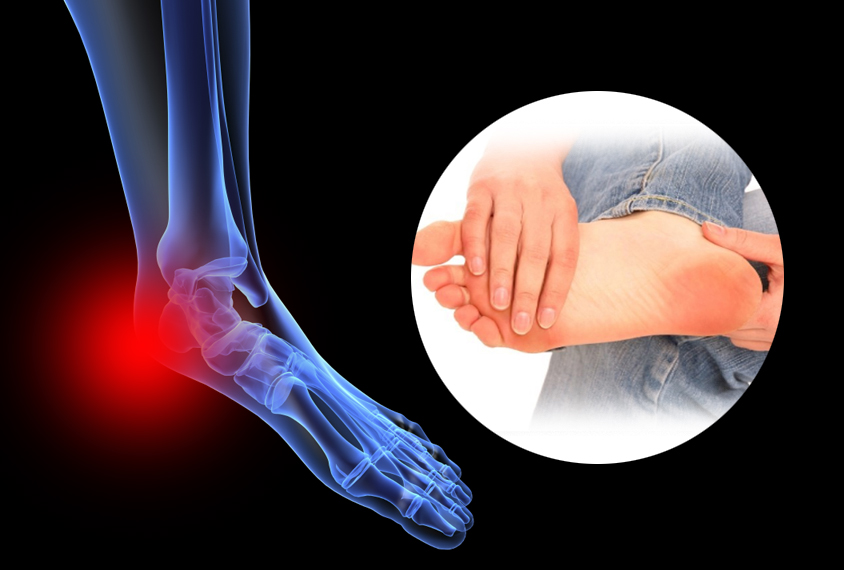

족저 근막염이란?

아침에 일어나 걸을 때 발바닥 통증을 느껴보신 적 있나요? 족저 근막염 증상 중 하나입니다.

이 외에도 발꿈치 내측의 압통, 서있을 때 뒤꿈치가 뻣뻣하고 찌릿함 등도 족저 근막염 증상입니다. 족저 근막염이 진행되면 오래 걷거나 운동을 한 후에도 통증이 나타납니다.

족저 근막은 종골에서 시작하여 발바닥 앞쪽으로 5개의 분지를 내어 발가락 기저부에 부착되는 강인하고 두꺼운 섬유 띠입니다.

이는 발의 아치를 유지하고 체중 부하 상태에서 발을 올리는데 도움을 줍니다. 족저 근막염은 족저 근막에 미세한 손상이 반복해서 발생하여 콜라겐이 변성되고 퇴행성 변화로 통증이 유발되는 질환입니다.

가장 흔하게 나타나는 족부 병변 중 하나로 뒤꿈치의 통증을 일으키는 질환입니다. 장시간 서있거나 과도한 운동 , 몸무게 증가, 하이힐 등 발에 스트레스가 증가하면 더 쉽게 발병합니다.